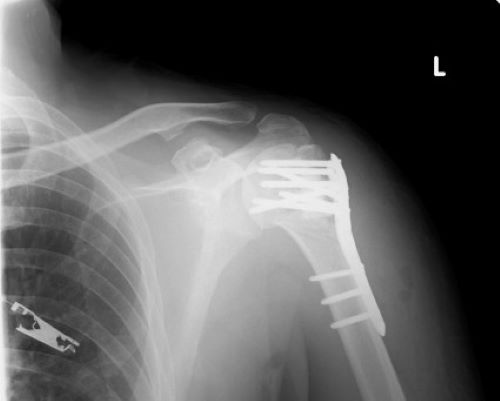

先日、左肩の抜釘、関節授動術の手術を受けました。写真の如く左肩に入っていたプレートと釘を取り、軟骨と硬くなっている筋を取り除く手術でした。昨年の7月コロナの第一波が収まりかけていた頃、飲酒に出かけ、縁石に躓き転倒し、左肩を骨折した際、治療の為に肩にプレートを挿入していたのです。昨年は手術後の全身麻酔が切れた途端、左肩に激痛が走り、術後1週間は頓服薬のお世話になったのですが、今回の術後は激痛もなく、痛みも随分楽で今の所、頓服薬は飲んでいません。昨年の術後は切除部位の筋肉が収縮し、左腕を上げると痛みが走り、クリニックで天井からの紐を引っ張る、肩の滑車訓練機のリハビリも痛いばかりであまり効果が出ず数カ月で通院を止めました。結局、会社の近くのバランス整体(https://balance--seitai.com/)でストレッチポールによる治療と自宅でストレッチポールで出来るリハビリを指導され腕が上がるように成りました。今回もバランス整体に通い、自宅でもストレッチポールでリハビリをしようと思っています。只、このリハビリで良い事が有りました。私は仕事がら、机上でパソコン作業をする事が多く、肩こりに悩まされていたのですが、毎朝ストレッチポールでリハビリする事で肩甲骨が広がり、肩こりが治ったのです。正に「ケガの功名」です。皆さんも是非お試しください。